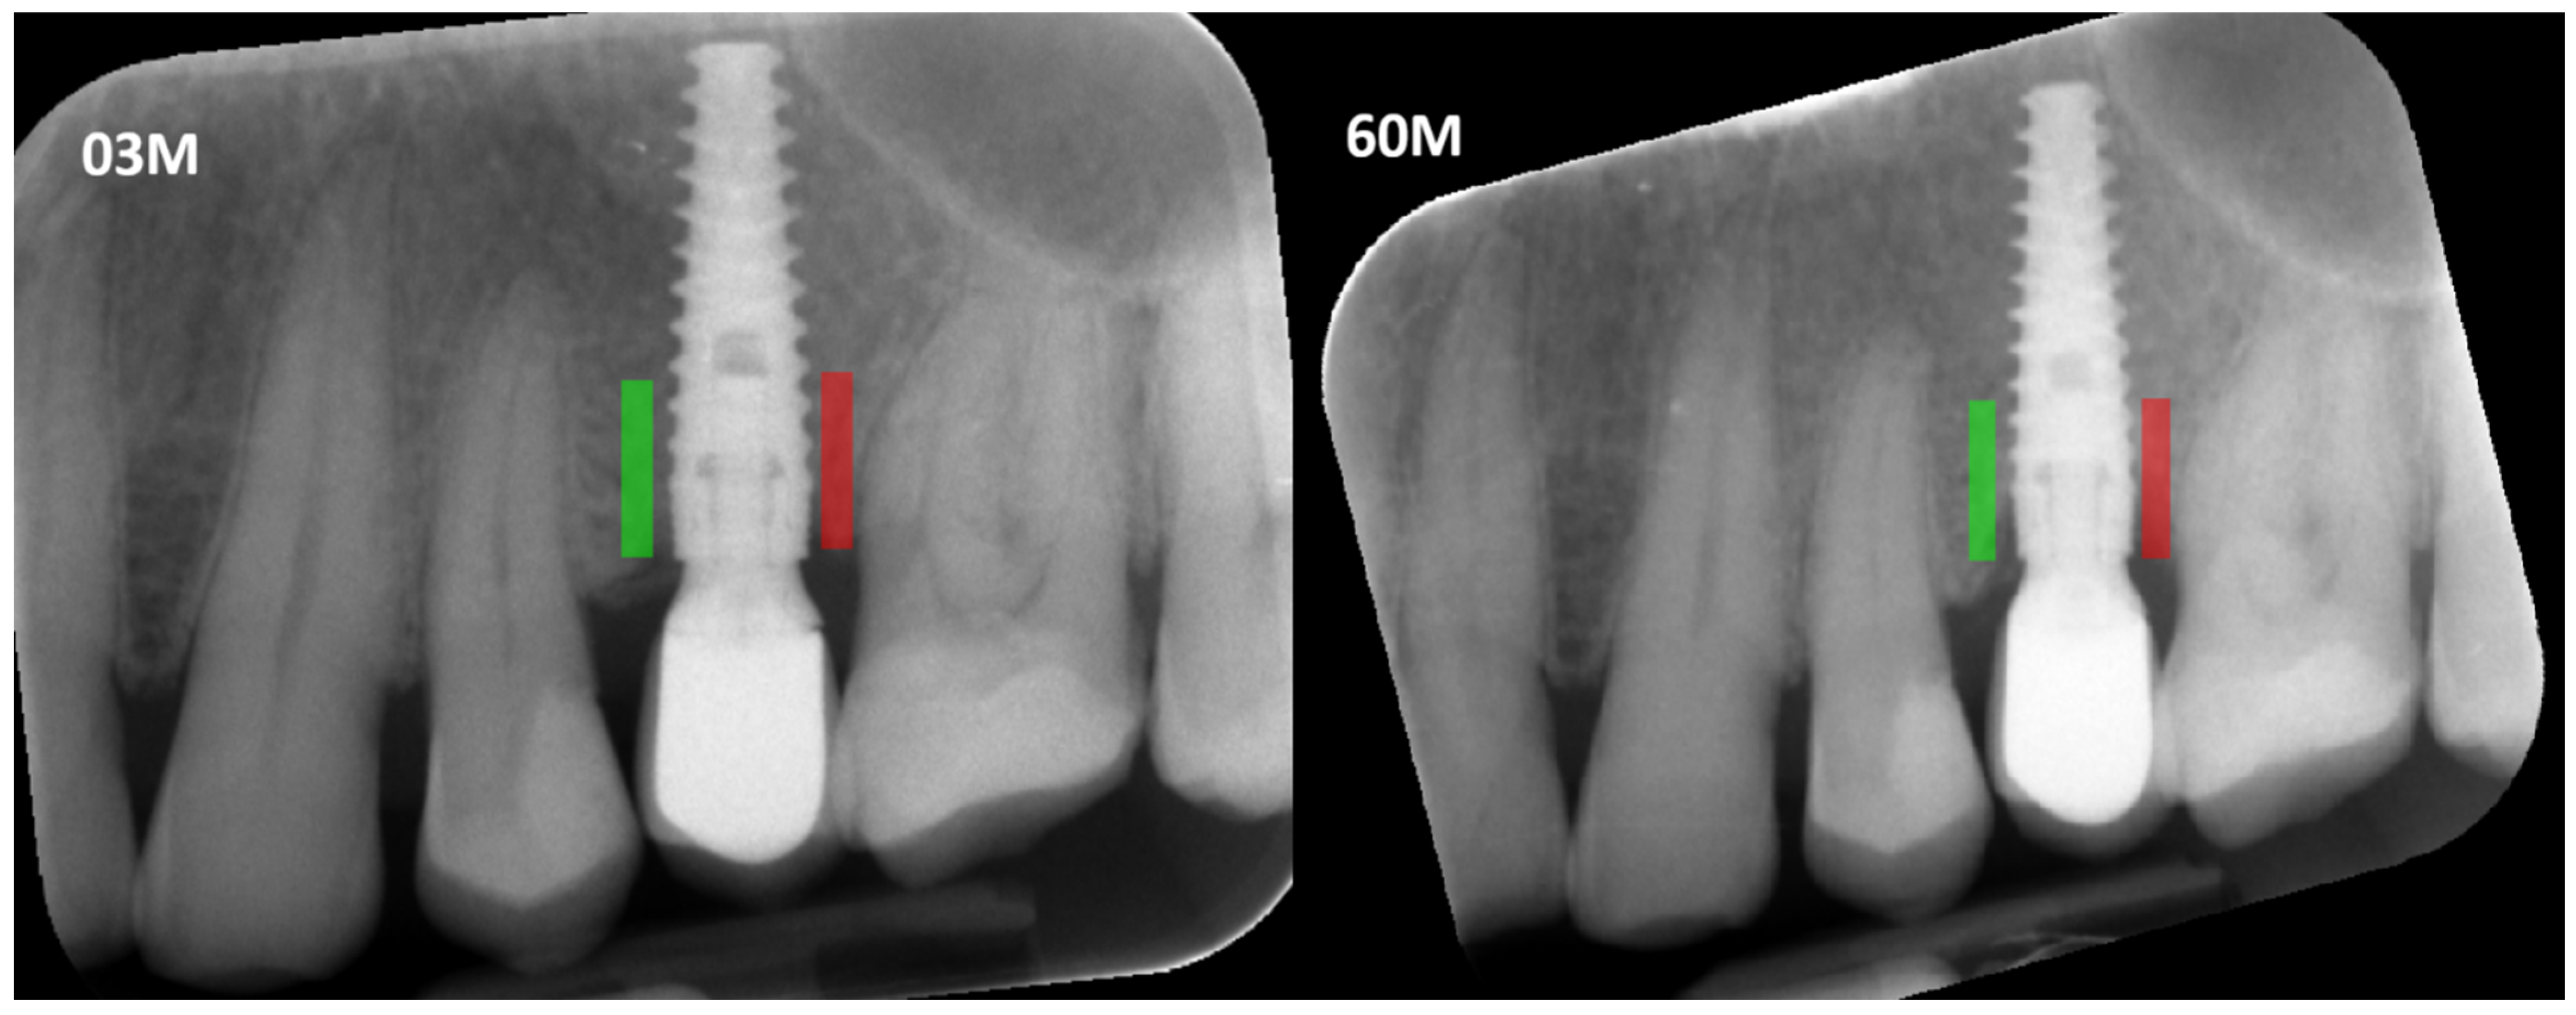

- The CI must be calculated on a defined Region of Interest (ROI) on the radiograph, and this ROI selection must be standardized. In our study, we standardized the ROI based on the method described by Kozakiewicz et al. [10], ensuring that the measurements are reliable and reproducible.